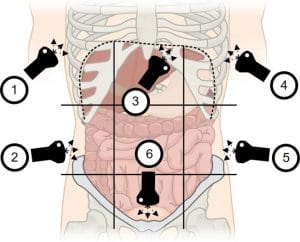

Chest POCUS

All individuals were evaluated by chest POCUS using the Mindray R Mobile Trolley equipment model UMT-150p and a convex probe under an abdominal software preset [8].  Chest POCUS was performed during the first 24 hours of diagnosis by a pulmonologist with seven years of experience, who was blinded to the clinical data or follow-up. Four thoracic areas per hemithorax were evaluated, including two anterior and two lateral (eight areas in total), with the patient in the supine position. The presence of lung sliding with an A-pattern was considered normal. More than three B-lines, the shred sign or other signs of consolidation, dynamic or static air bronchograms, or pleural effusion were considered abnormal findings. Pleural effusion was described in terms of location, echogenic pattern (simple or complex) [9], volume in mL using the Balik´s formula (volume, ml= measured distance between parietal and visceral pleura in mm x 20) [10], distance in cm between the parietal and visceral pleura, and number of intercostal spaces (ICS) occupied by fluid (1 ICS=small pleural effusion, 2-3 ICS=moderate pleural effusion, ≥4 ICS=large pleural effusion). A pleural effusion of less than 2 cm (distance between the visceral and parietal pleura) was deemed insufficient for aspiration.